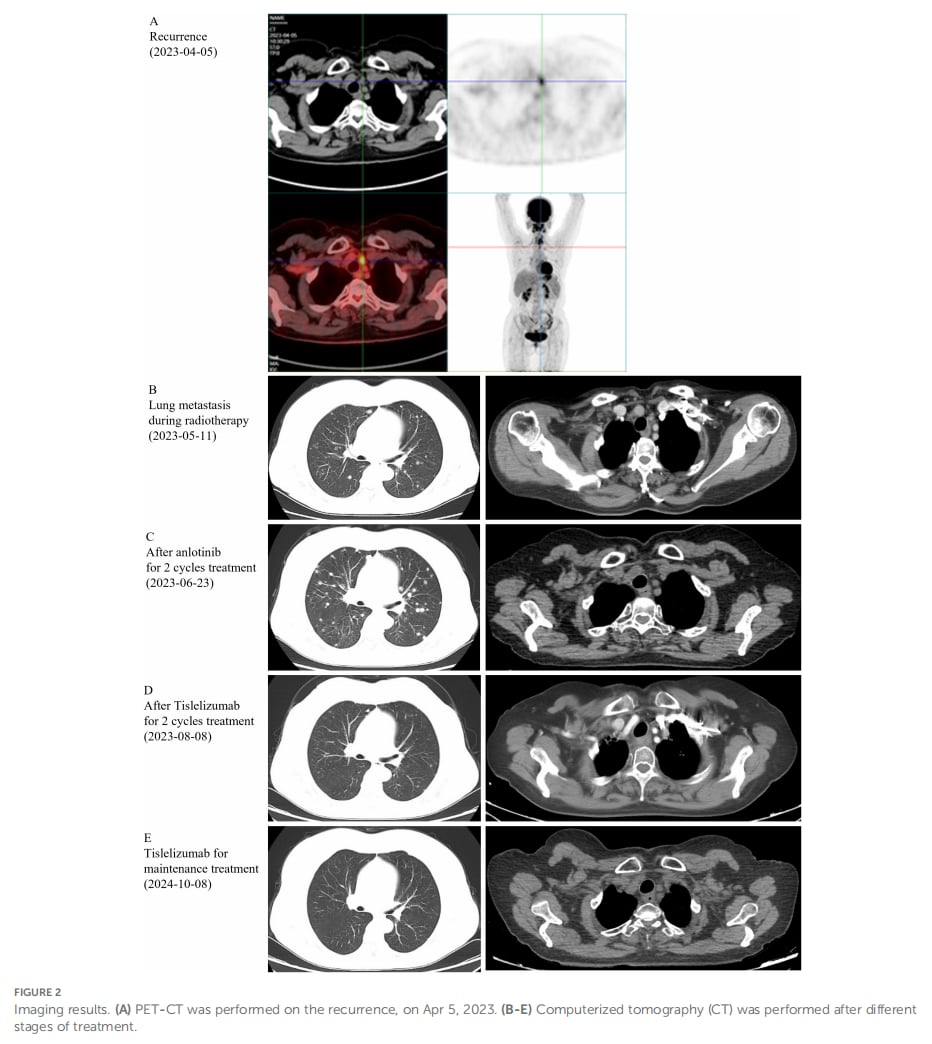

令人欣喜的是,在接受替雷利珠单抗治疗后,患者颈部转移淋巴结及肺部转移瘤显著缩小,并持续缓解了14个月,最终达到了完全缓解的状态。更重要的是,在整个免疫治疗过程中,患者并未发生任何严重的免疫检查点抑制剂相关不良事件。

▲图2 影像结果